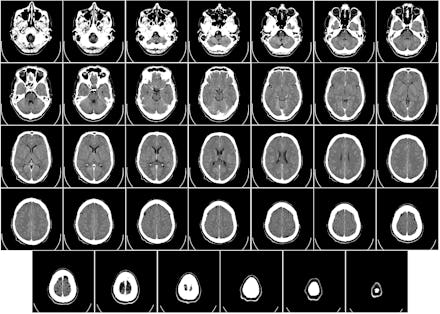

The study Chamberlain conducted compared the brains of 21 art students with 23 non-artists. Using neuroimaging the study found that individuals who displayed more skill in observational drawing had more grey and white matter in one very specific part of the brain — the precuneus region of the parietal lobe — than those who scored low on drawing tests. In sum, the findings suggest that, yes, artistic ability might be innate.

The parietal lobe, located just behind the frontal lobe, processes sensory information, including sense of touch and spatial sense. It would make sense then that people with more developed parietal lobes are better at translating visual cues into artistic representations. The more skilled illustrators also showed more grey and white matter in the cerebellum and in the supplementary motor area.